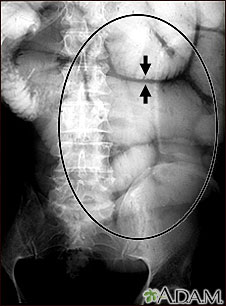

Ileus - x-ray of bowel distension

This abdominal x-ray shows thickening of the bowel wall and swelling (distention) caused by a blockage (obstruction) in the intestines. A solution containing a dye (barium), which is visible on X-ray, was swallowed by the patient (the procedure is known as an upper GI series).